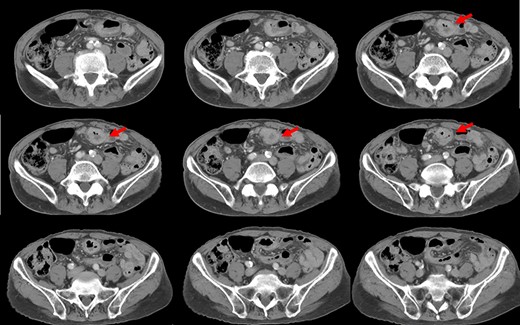

Preoperative computed tomography (CT) revealed a tumor in the sigmoid colon accompanied by some regional lymph node swelling (Fig. 1). It also showed that the IVC ascended vertically along the left side of the abdominal aorta. After connecting with the left renal veins, the left-sided IVC crossed the abdominal aorta anteriorly to join the normal prehepatic segment of the IVC (Figs 2 and 3). Coronal CT showed that the descending colon misplaced at the abdominal midline and the sigmoid colon in the right upper abdomen (Fig. 4). The preoperative diagnosis was thus sigmoid colon cancer with left-sided IVC and PDM.

Coronal reformation of the CT image shows precisely how the left-sided IVC (arrows) ascended vertically along the left side of the abdominal aorta and crossed anterior to the aorta.